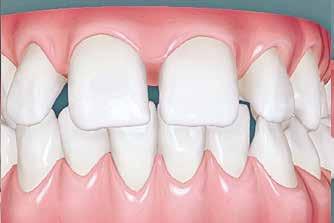

Lány páciensem I. fázisú kezelését 10 évesen kezdtük el bimaxilláris funkciós, kivehető készülékkel. Megfigyelhetőek a class 2-es eltérésnél tipikusan jellemző szűk felső és alsó fo-

gívek, valamint a nagy overjet, a mandibula disztál helyzete, továbbá a felső metszőfogak protrúziója, amelynek kialakulásához sokszor hozzájárul az ujjszopás is (1-3. képek)